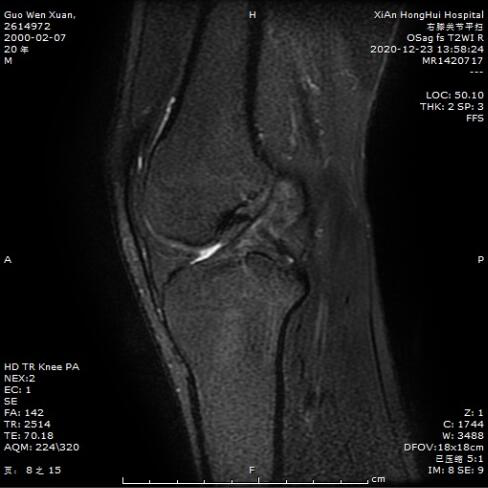

普通矢状位扫描下前交叉韧带显示不清

沿韧带走行斜矢及斜冠状位扫描,可见前交叉韧带前内侧束连续,后外侧束损伤